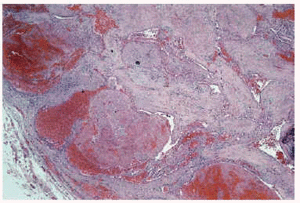

Algunas de las tumoraciones blandas, las que producían dolor, se extirparon y se realizó estudio histopatológico que demostró la presencia de espacios anfractuosos tapizados por endotelio y a menudo ocupados por trombos y hemorragias (fig. 3). En el abundante tejido interpuesto, además de fibrosis hay haces de células fusiformes con vacuolización citoplasmática (fig. 4) que caracteriza la entidad conocida como hemangioendotelioma, o actualmente hemangioma de células fusiformes.

Fig. 4.--Detalle de las células fusiformes con espacios anfractuosos tapizados por endotelio y ocupados por trombos y hemorragia situadas entre las luces.